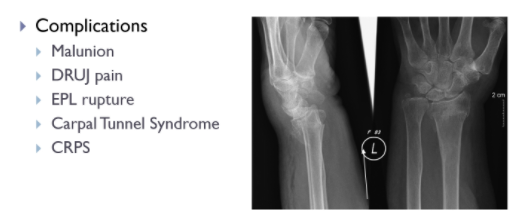

what are the complications of a colles fracture?